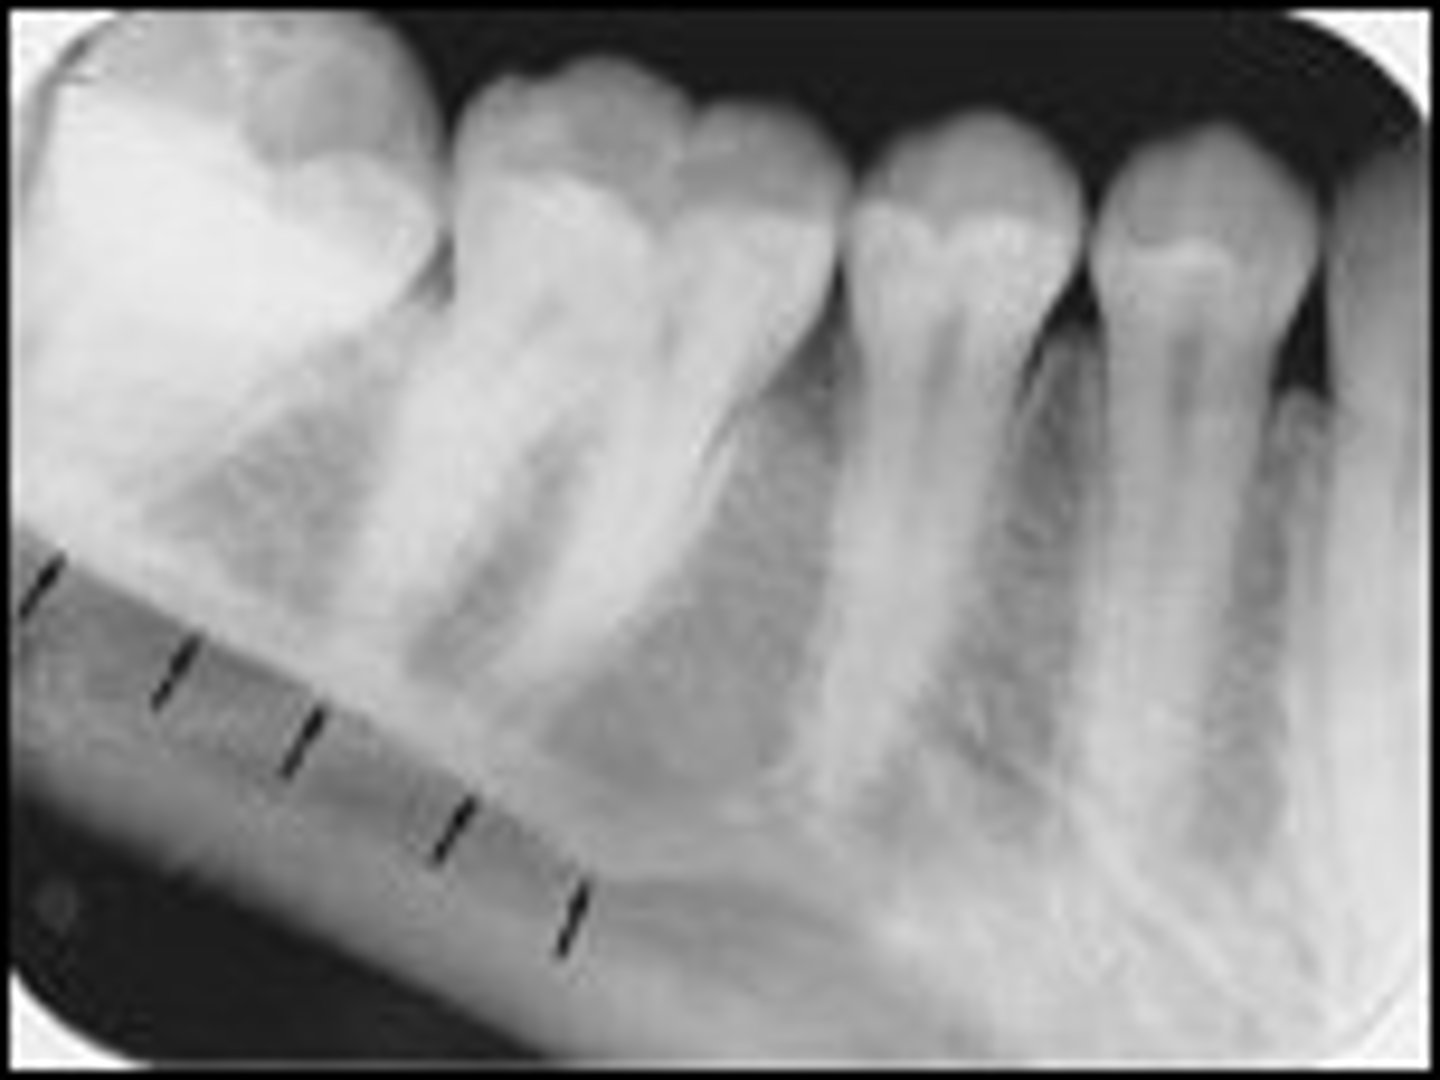

what is this?

what is this radiolucent area in the image?